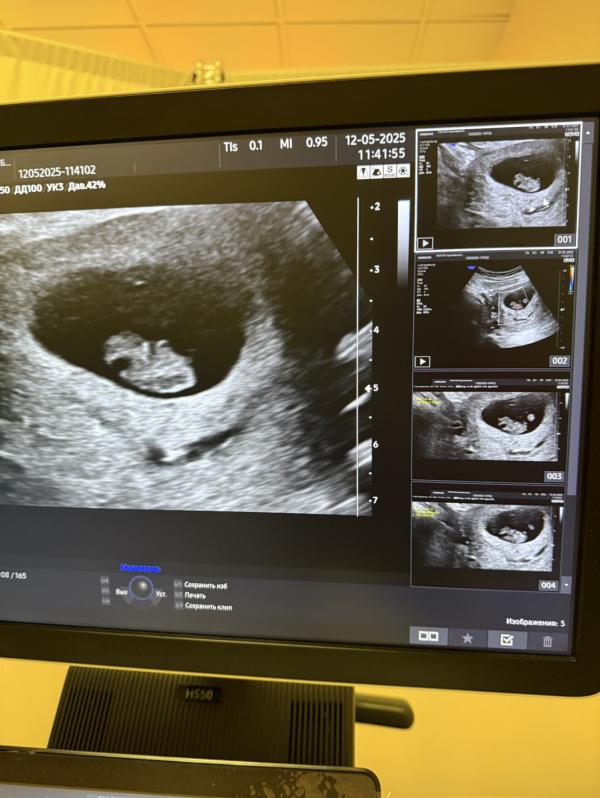

Гематома куда-то рассосалась сама! Я счастлива, 😊 что все в порядке, а думала, что в больницу положат, 🚐 но все обошлось. 😅😌 Я теперь успокоилась и буду спать спокойно, завтра пойду сдавать анализы и буду вставать на учет по беременности. По узи срок 8.1 🍒 Уже машет ручками нам 😍

Вообще по узи я ставила, но я знаю дату зачатия 😆и сейчас мне подтвердили что все таки от даты зачатия срок, расходится в неделю..